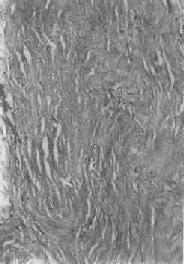

图1-18 肝细胞脂肪变性 肝细胞胞浆内出现大小不等的脂肪空泡;右上角为饿酸染色的脂肪细胞, 脂滴染成黑色 (2)心肌脂肪变性:心肌在正常情况下可含有少数脂滴,脂肪变性时脂滴明显增多。镜下,脂肪空泡较细小,呈串珠状成排排列,主要位于肌纤维Z带附近和线粒体分布区。常为贫血和中毒的结果。在严重贫血时,可见心膜下尤其是乳头肌处出现成排的黄色条纹,与正常心肌的暗红色相间排列,状若虎皮斑纹,故有“虎斑心”之称。严重感染、白喉外毒素以及其他毒物(如磷、砷、氯仿等)也能引起心肌的弥漫性脂肪变。肉眼观,心肌均匀变浊,略呈黄白色。但通常心功能并不受明显影响。显著的心肌脂肪变性如今并不常见。 (3)肾脂肪变性;在严重贫血、缺氧和中毒过程中,或肾小球毛细血管通透性升高时,肾小管特别是近曲小管的上皮细胞可吸收漏出的脂蛋白而导致脂肪变性。脂滴起初多位于细胞基底部。肉眼观,肾稍肿大,切面上可见皮质增厚,略呈浅黄色。 2.玻璃样变性 又称透明变性(hyaline degeneration),为十分常见的变性,主要见于结缔组织、血管壁,有时也可见于细胞内。 1.结缔组织玻璃样变:常见于纤维瘢痕组织、纤维化的肾小球,以及动脉粥样硬化的纤维性瘢块等。此时纤维细胞明显变少,胶原纤维增粗并互相融合成为梁状、带状或片状的半透明均质,失去纤维性结构(图1-19)。质地坚韧,缺乏弹性。玻璃样变的发生机制尚不甚清楚,有人认为在纤维瘢痕老化过程中,原胶原蛋白分子的交联增多,胶原原纤维也互相融合,其间并有较多的糖蛋白积聚,形成所谓玻璃样物质;也有人认为可能由于缺氧、炎症等原因,造成局部pH升高或温度升高,致使原胶原蛋白分子变性成明胶并互相融合所致。 2.血管壁玻璃样变:这种改变常见于高血压病时的肾、脑、脾及视网膜的细动脉。此时,可能是由于细动脉的持续性痉挛,使内膜通透性增高,血浆蛋白得以渗入内膜,在内皮细胞下凝固成无结构的均匀红染物质。此外,内膜下的基底膜样物质增多。这些改变使细动脉的管壁增厚、变硬,管腔变狭,甚至闭塞(图1-20),此即细动脉硬化症(arteri-olosclerosis),可引起肾及脑的缺血。 3.细胞内玻璃样变:亦称为细胞内玻璃样小滴变性。这种情况常见于肾小球肾炎或其他疾病而伴有明显蛋白尿时。此时肾近曲小管上皮细胞胞浆内可出现许多大小不等的圆形红染小滴(图1-21),这是血浆蛋白经肾小球滤出而又被肾小管上皮细胞吞饮的结果,并在胞浆内融合成玻璃样小滴,以后可被溶酶体所消化。此外,在酒精中毒时,肝细胞核周胞浆内亦可出现不甚规则的红染玻璃样物质。电镜下,这种物质由密集的细丝构成,据认为可能是细胞骨架中含角蛋白成分改变的结果,并被称为Mallory小体。

图1-19 纤维瘢痕组织的玻璃样变 胶原纤维变粗,互相融合呈均质梁状 3.纤维素样变性(纤维蛋白样变性)为间质胶原纤维及小血管壁的一种变性。病变部位的组织结构逐渐消失,变为一堆境界不甚清晰的颗粒状、小条或小块状无结构物质,呈强嗜酸性红染,状似纤维素,并且有时呈纤维素染色,故称此改变为纤维素样变性(fibrinoid degeneration),其实为组织坏死的一种表现,因而也称为纤维素样坏死(fibrinoid necrosis)。 纤维素样变性主要见于急性风湿病及结节性动脉周围炎等变态反应性疾病。至于所谓纤维素样物质的性质和形成机制,至今尚无统一意见。一般认为,在早期,结缔组织基质中有PAS阳性的粘多糖增多,以后纤维崩解为碎片,从而失去原来的组织结构而变为纤维素样物质。此外,还有免疫球蛋白增多,有时还有纤维蛋白增多。这种改变可能是抗原抗体反应时形成的生物活性物质使间质受损、胶原纤维崩解所致。同时,附近小血管也可受损,引起通透性升高、血浆渗出,并在组织凝血系统的酶的催化作用下,使血浆纤维蛋白原转化为纤维蛋白。